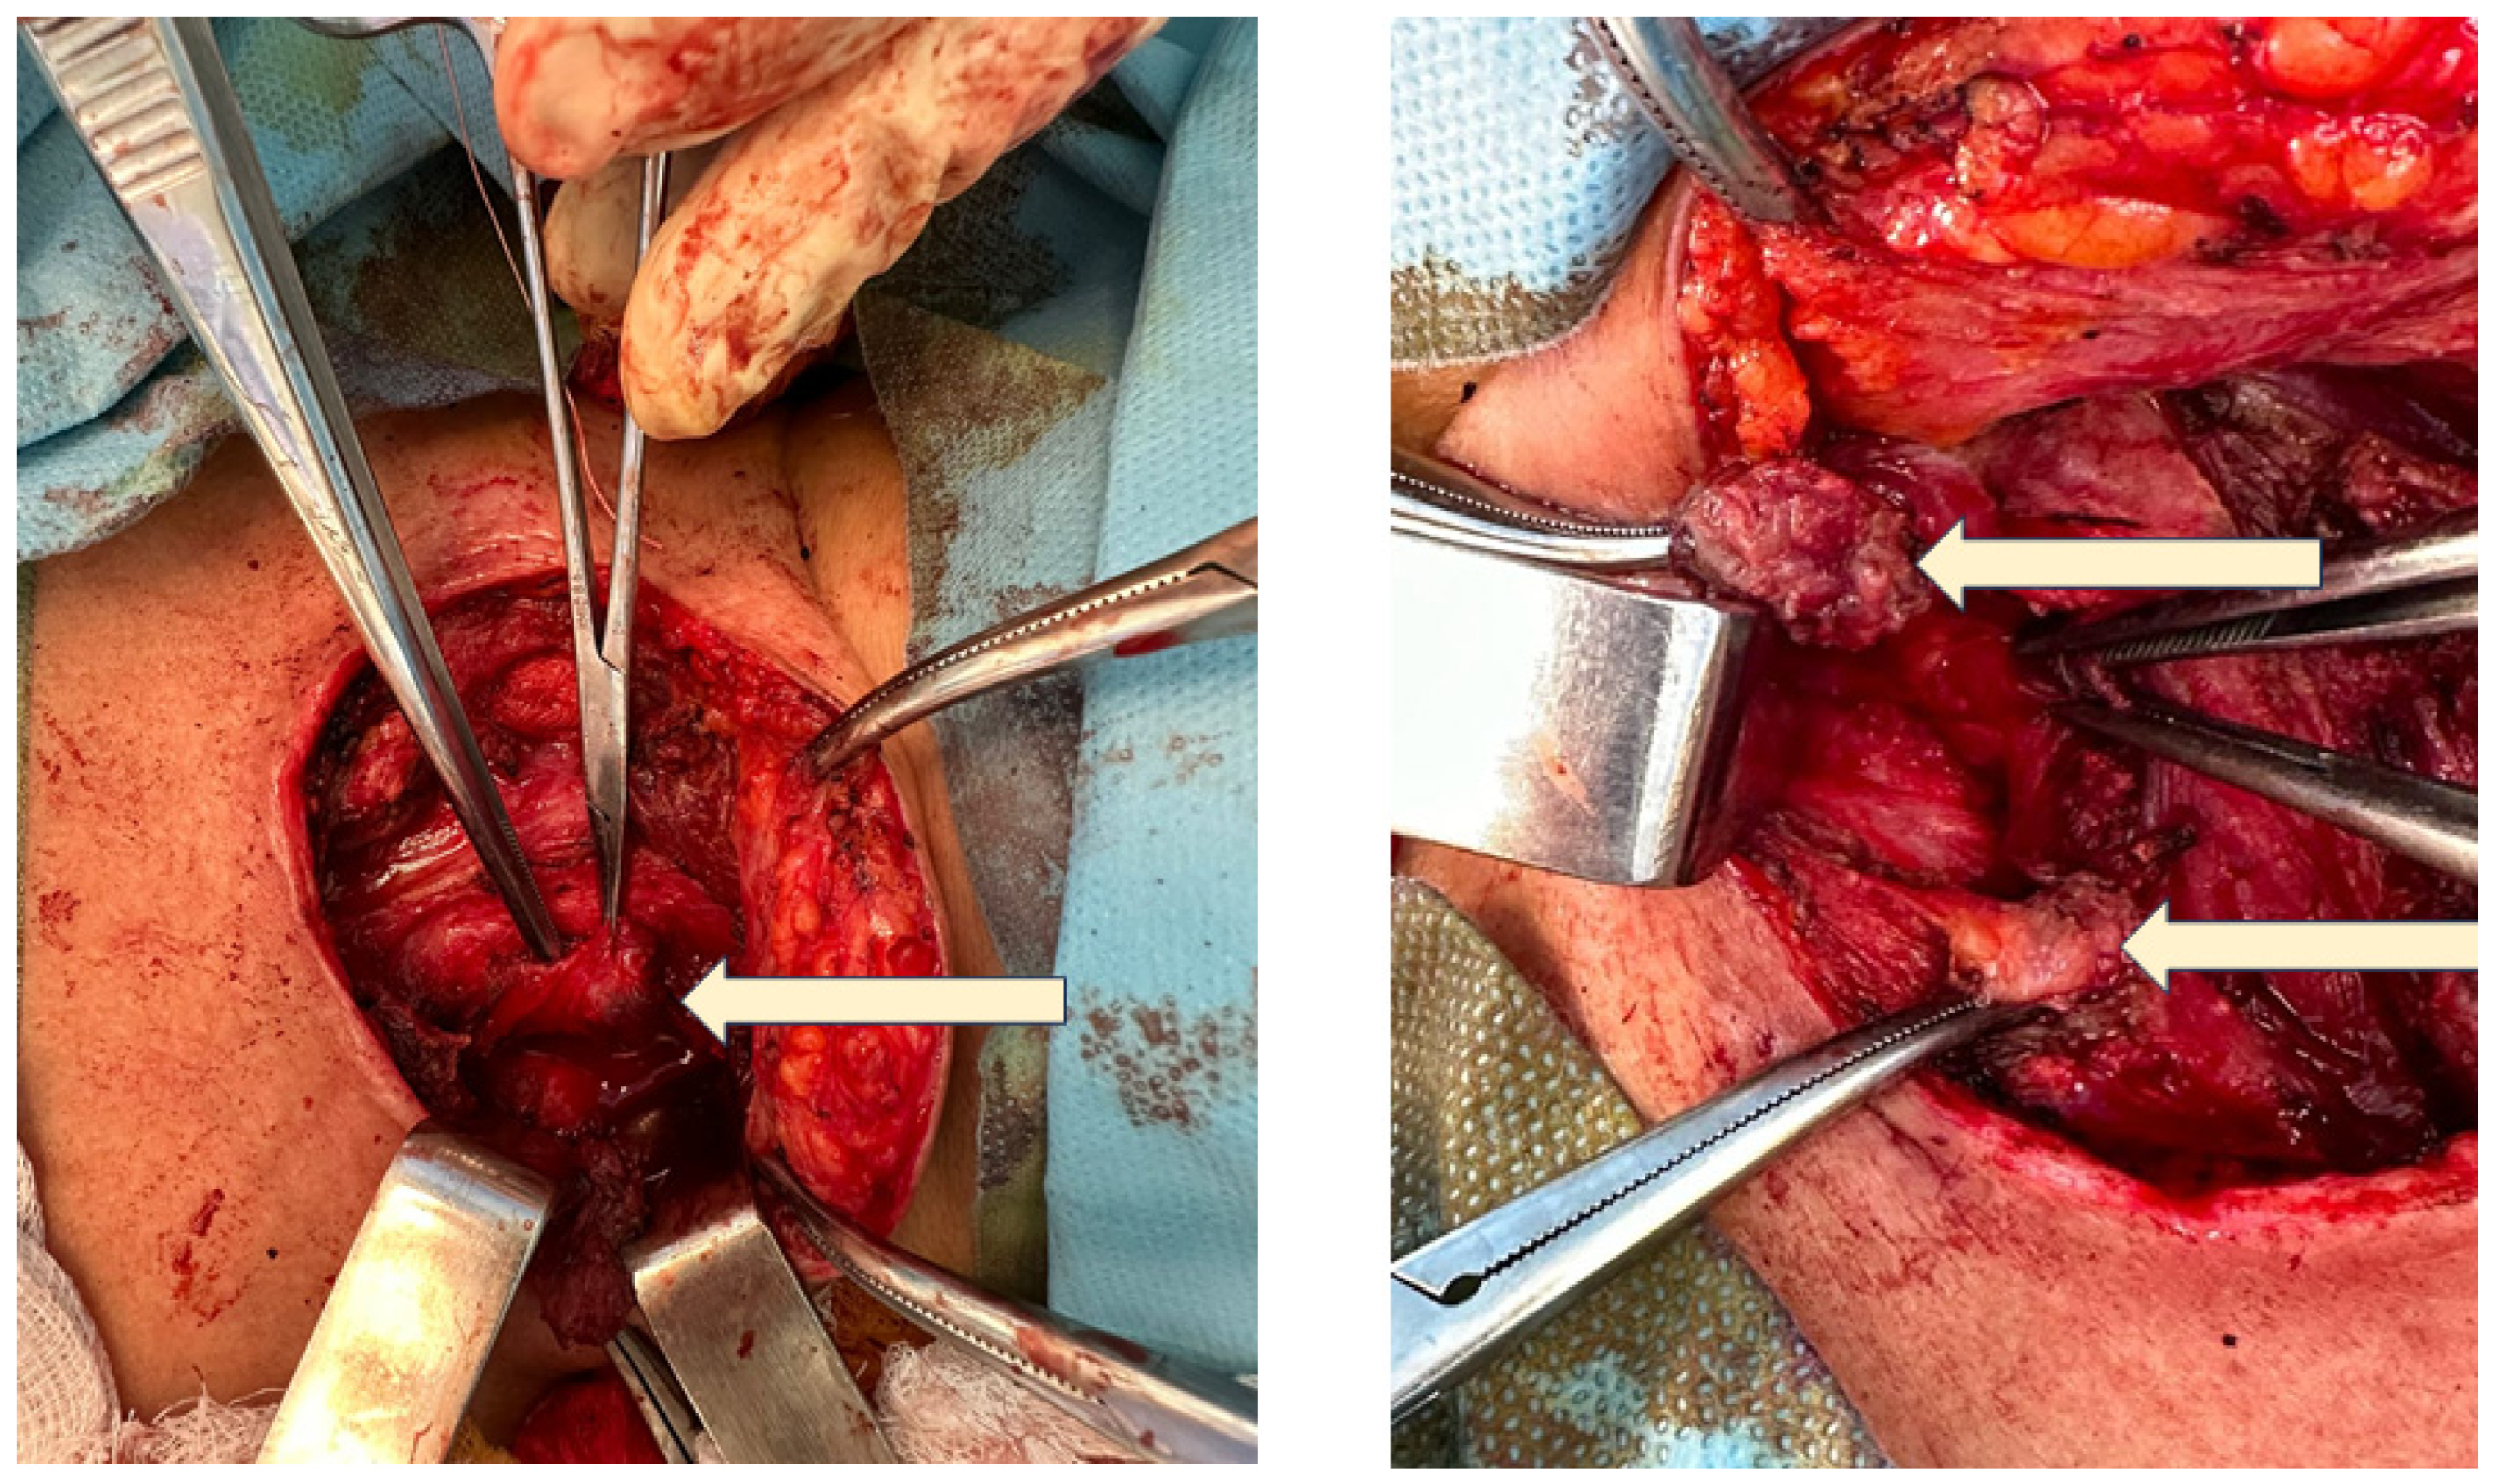

4.1.4. Redo Thyroidectomy

4.1.5. Post-Redo Outcome